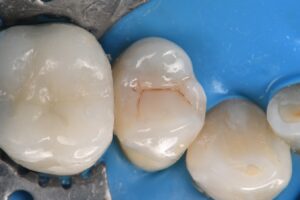

It’s always difficult to decide which vertical hairline fractures to chase in a compromised peripheral enamel rim. Chasing and selectively removing the significant hairline fractures with penetration past the DEJ ensures that these superhighways are sealed and don’t have an opportunity to seed caries insidiously.